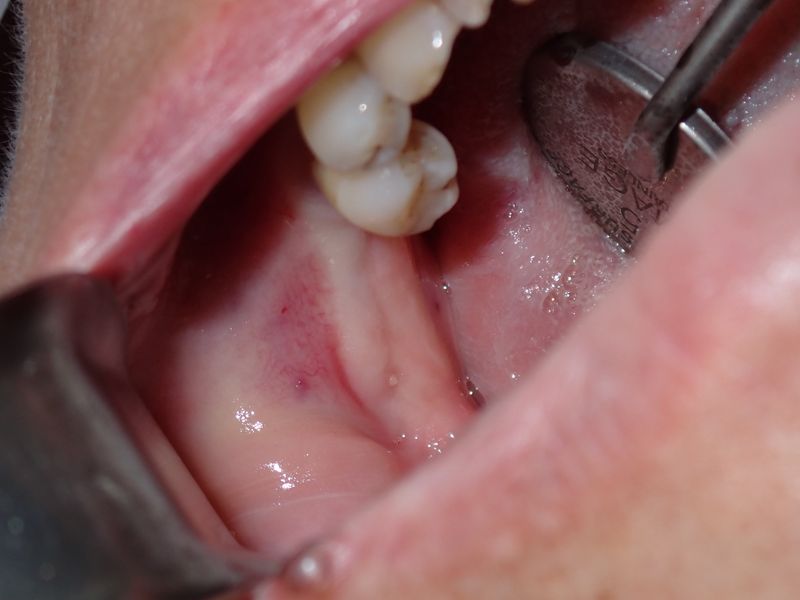

fredlibc | profile | all galleries >> Galleries >> TZeng - 36 and 37 tree view | thumbnails | slideshow

PA070001.JPG (1 of 9)